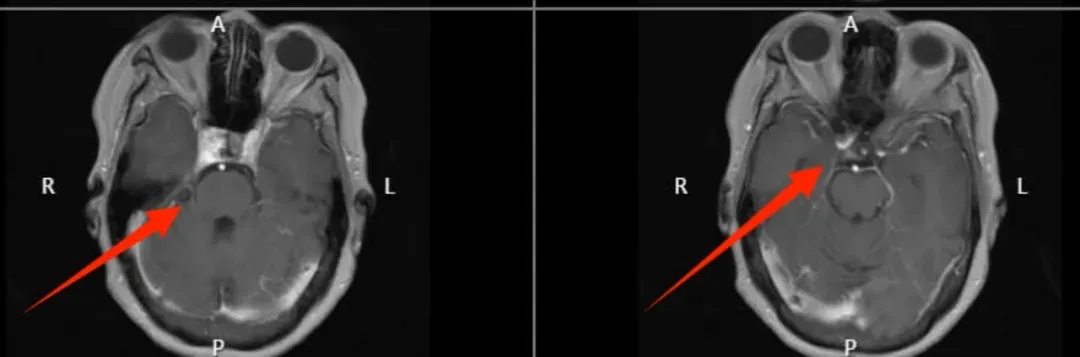

2023年5月15日陈女士顺利入院,经过系列检查以及医生评估确诊为鞍区肿瘤。

林志雄教授表示,患者颅内肿瘤的位置手术难度极大,且术后并发症多,可能手术过后,眼睛无法睁开或者出现复视的症状。同时结合患者本人情况,陈女士有3年余的糖尿病病史并且畏惧开颅手术。所以经过医生们的讨论,决定予以伽玛刀治疗。

治疗前影像

治疗后一年复查

患者本人表示,伽玛刀治疗全过程都是无痛的,不用开刀,自己轻松,也为家庭术后护理减轻负担,就像做核磁共振一样睡一觉就好了,现在一年多了,肿瘤有明显萎缩,真的太好了,非常感谢福建三博医生护士们的辛勤付出。